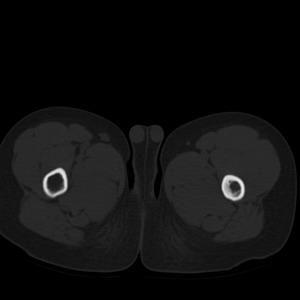

标题: PED1884:患者,男性,7岁。因右髋疼痛5天,而来院检查。 [打印本页]

标题: PED1884:患者,男性,7岁。因右髋疼痛5天,而来院检查。

因右髋疼痛5天,而来院检查。

我们考虑:1、骨皮质增厚症。2、畸形性骨炎。3、骨纤。

右髋疼痛,左侧病变,看来无症状。

支持左股骨上段骨纤维异常增殖症可能性大.

考虑左股骨上段骨纤维异常增殖症。